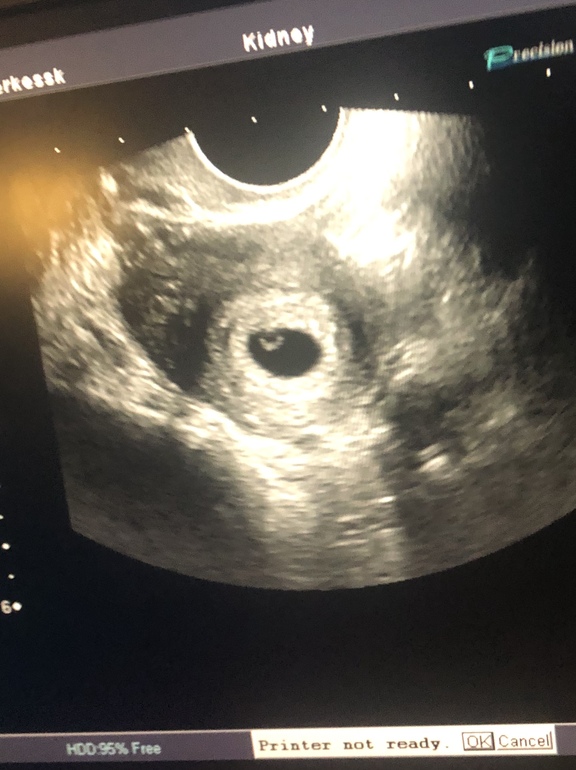

УЗИ, КТГ, доплерЗдравствуйте, девочки)) была сегодня на узи,

Все в порядке, тьфу-тьфу , мы растём . Переживаю только что эмбриона не видно и сердечко пока не слышно 😔

Ну у меня пя увидели в 4 недели, овуляция была на 12-14 дц где-то, точно не скажу

У меня в 4-5 недель тоже только ПЯ с ЖМ увидели, через неделю эмбриона с ЧСС 125 и КТР 4,6 мм. А ещё через неделю уже 14 мм КТР и ЧСС 178. Даже головку и ручки видно)) Так что у вас всё впереди)